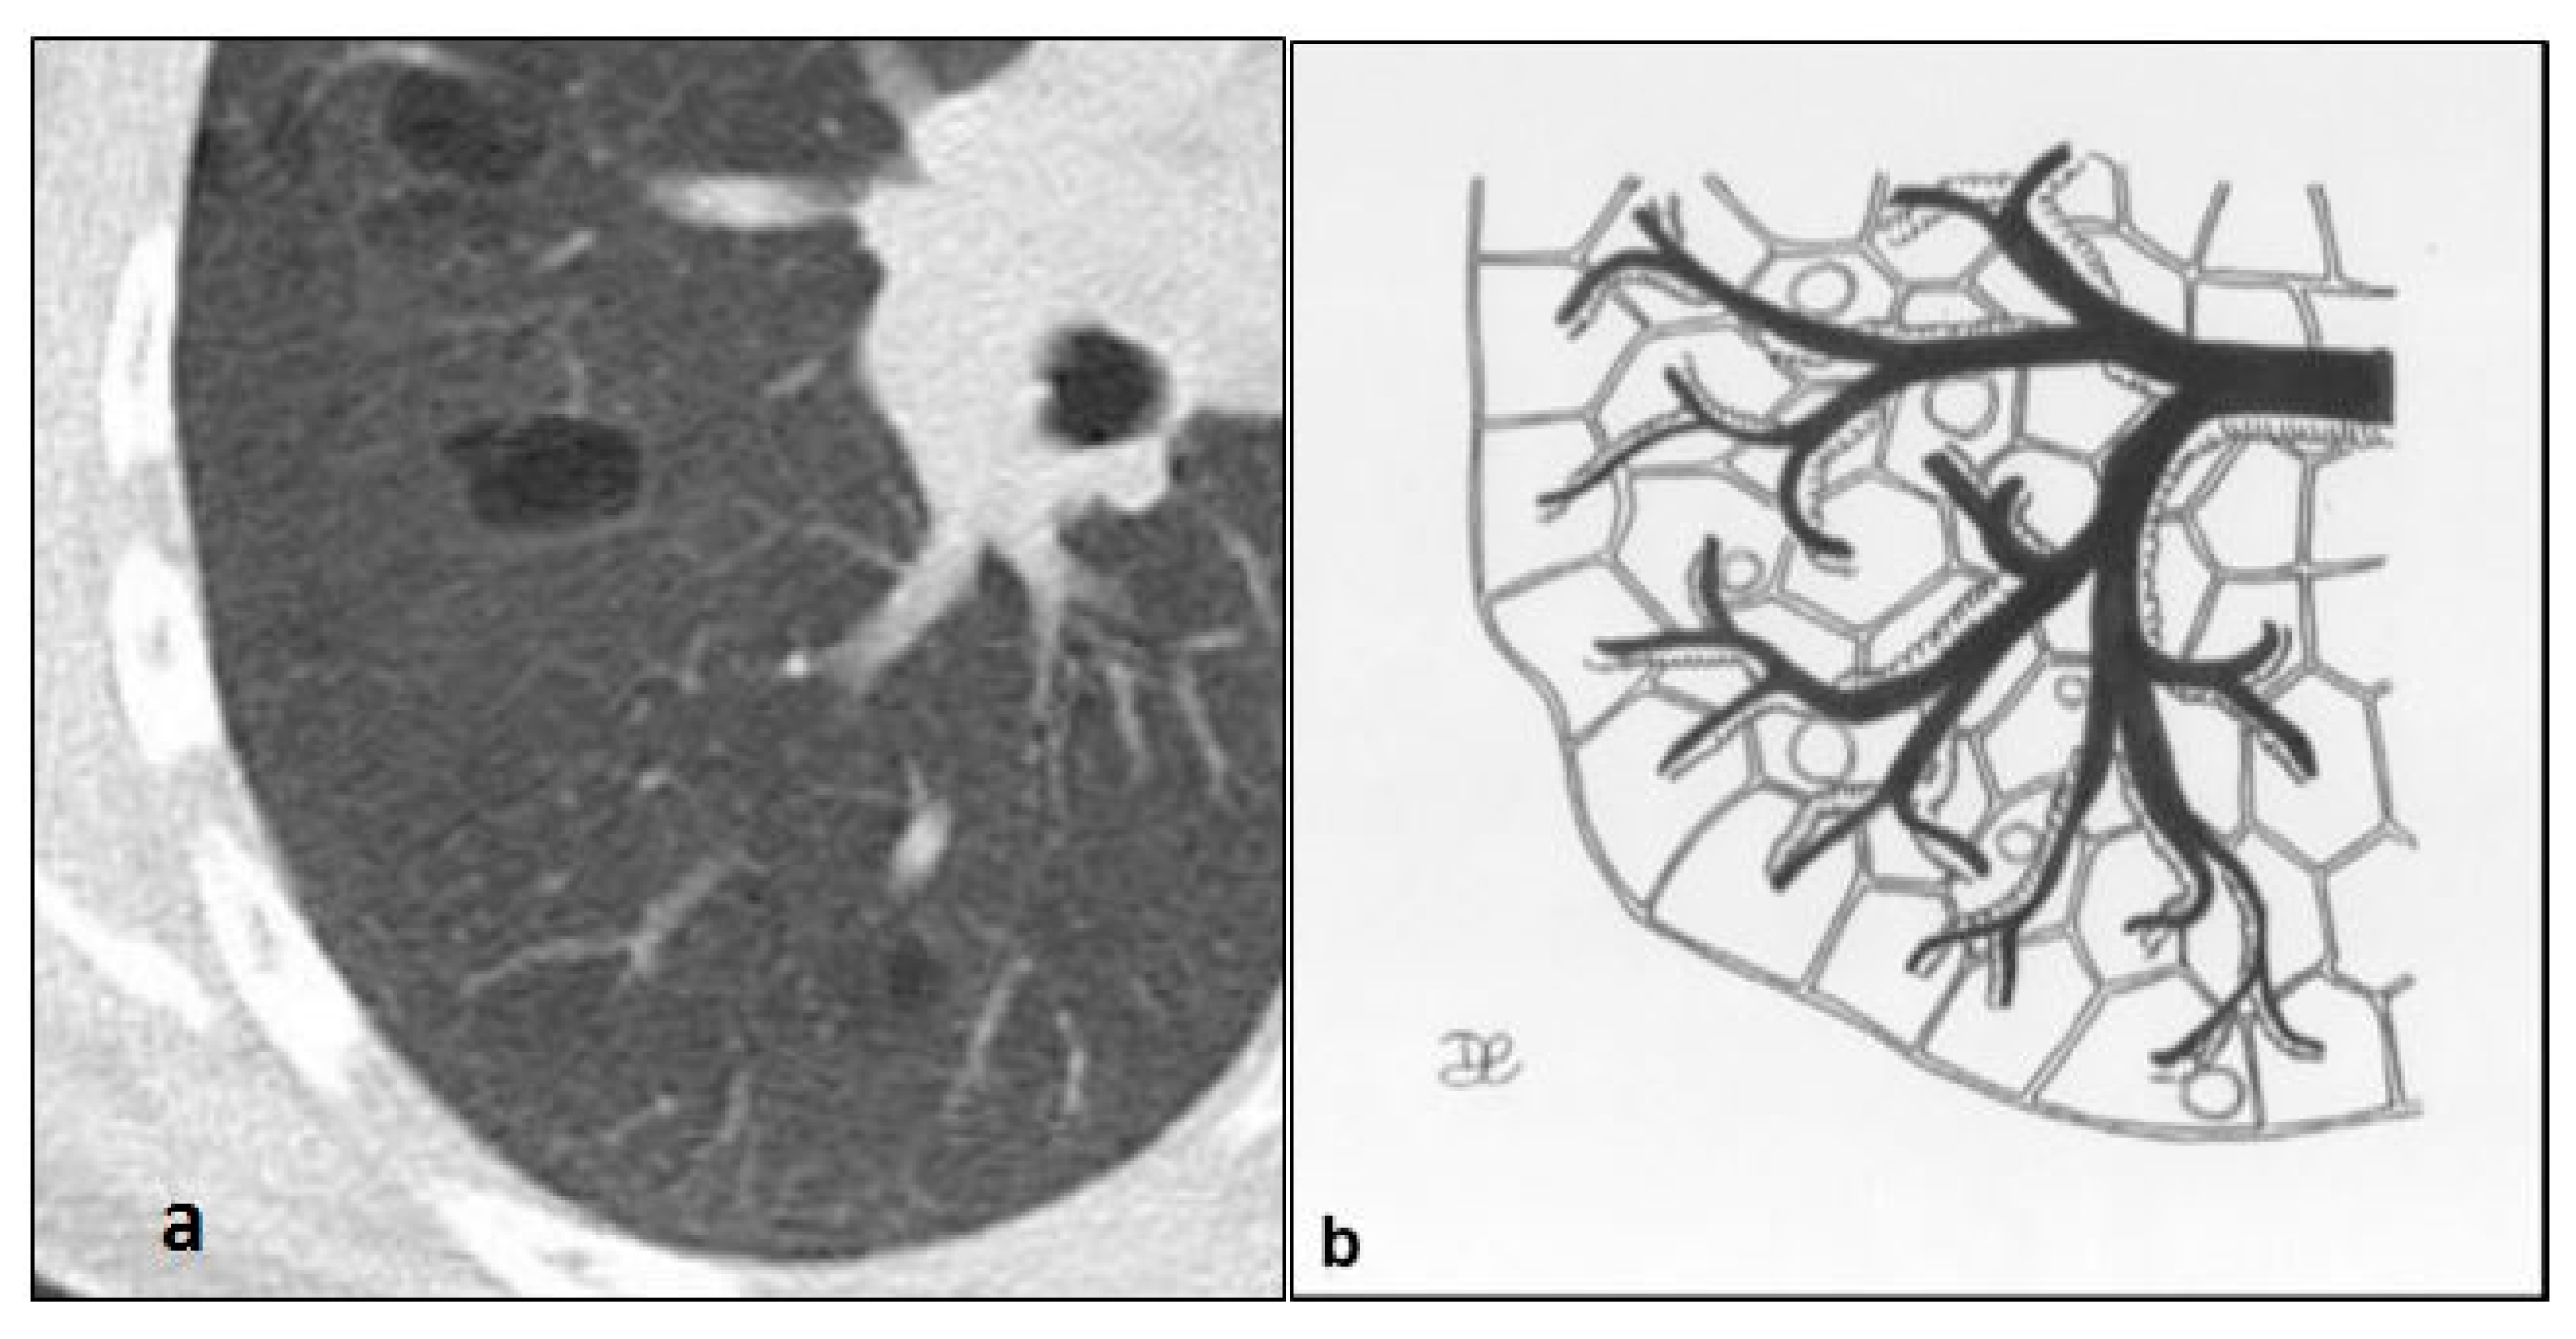

Figure 8. LIP cysts pattern (a): multiple cysts, with size ranging from 10 to 30 mm and thin walls, predominantly in peribroncovascular regions (b).

In LIP, cysts result from dilation of the airways above the stenosis, which is secondary to lymphocytic infiltration of the bronchiolar wall; these formations have thin walls and regular distribution, predominantly in peri-vascular regions, with involvement of the central portion of the lung. The cysts show variable size, ranging from few millimeters to 3 cm [27] (Figure 8 and Figure 9). On chest radiographs, a fine linear or reticular pattern may be found. In the acute phase, CT scan reveals pulmonary cysts and additional findings such as ground-glass opacities with a reticular pattern or small centrilobular nodules with low density, subpleural and peri-lobular nodules with higher density or consolidation [28]. LIP usually responds to steroid or immunosuppressive therapy, so that these opacities may regress in chronic disease; peri-vascular cysts could remain the only residual finding [29]. In some cases, LIP cases complicated with pulmonary fibrosis or that evolved into lymphoma have been described [30].